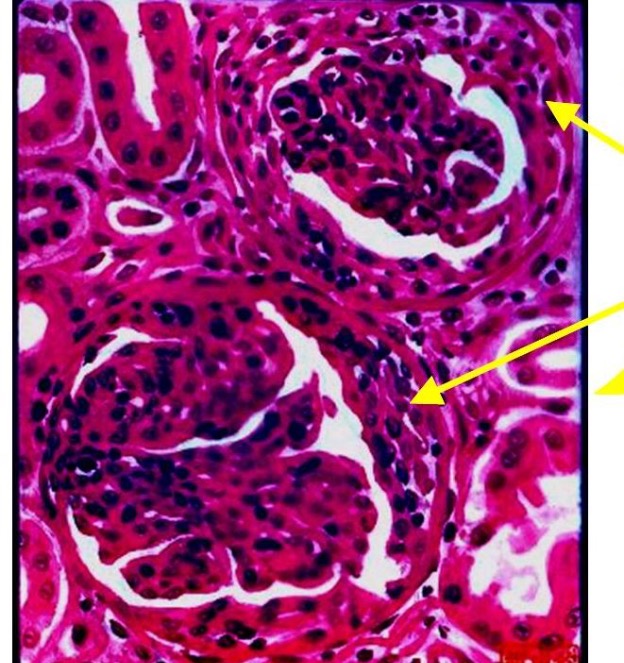

160.出现箭头所指图1、2改变的可能的肾炎是